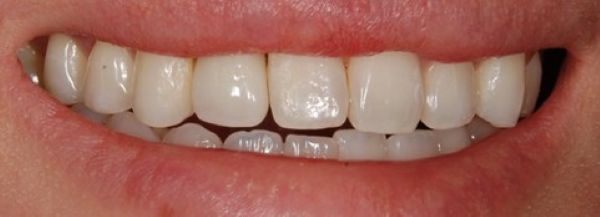

こちらが補綴物をセットした時の写真です。

患者様は

「以前、乳歯だった時はグラグラするのが心配で、噛むときに気にしながら食べていましたが、今は気にせず食事ができる様になりました。」

「乳歯が他の歯と比べると小さいことで見た目も気になっていたのですが、現在は微笑んだ時の歯の並びが気に入った。」

とおっしゃってくださいました。